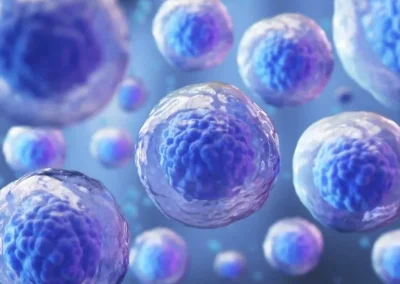

Existen diferentes tipos de células madre, y la medicina regenerativa las aplica de acuerdo con sus valiosas cualidades.

- Células madre embrionarias (ESCS). Se obtienen de blastocistos, que solo están presentes en las primeras etapas después de la fecundación; y tienen la capacidad de transformarse en cualquier tipo de célula, incluso en un organismo completo. Por ello, se emplea en la reparación de tejidos cardíacos, hepáticos y neuronales.

- Células madre pluripotentes inducidas (IPSCS). Son células somáticas reprogramadas a un estado pluripotente. Esto significa que se puede convertir en cualquier tipo de tejido como músculo, hueso o sangre; sin embargo, no tiene la capacidad de formar un organismo completo. Con el uso de este tipo de células, no se presentará el rechazo inmunológico.

- Células madre adultas (ASCS). Este grupo de células madre incluye las células madre mesenquimales (MSCs), las cuales son capaces de diferenciarse en varios tipos de células, como osteocitos, adipocitos y condrocitos. Y son las más utilizadas en la reparación de huesos, cartílagos y tejido miocárdico.